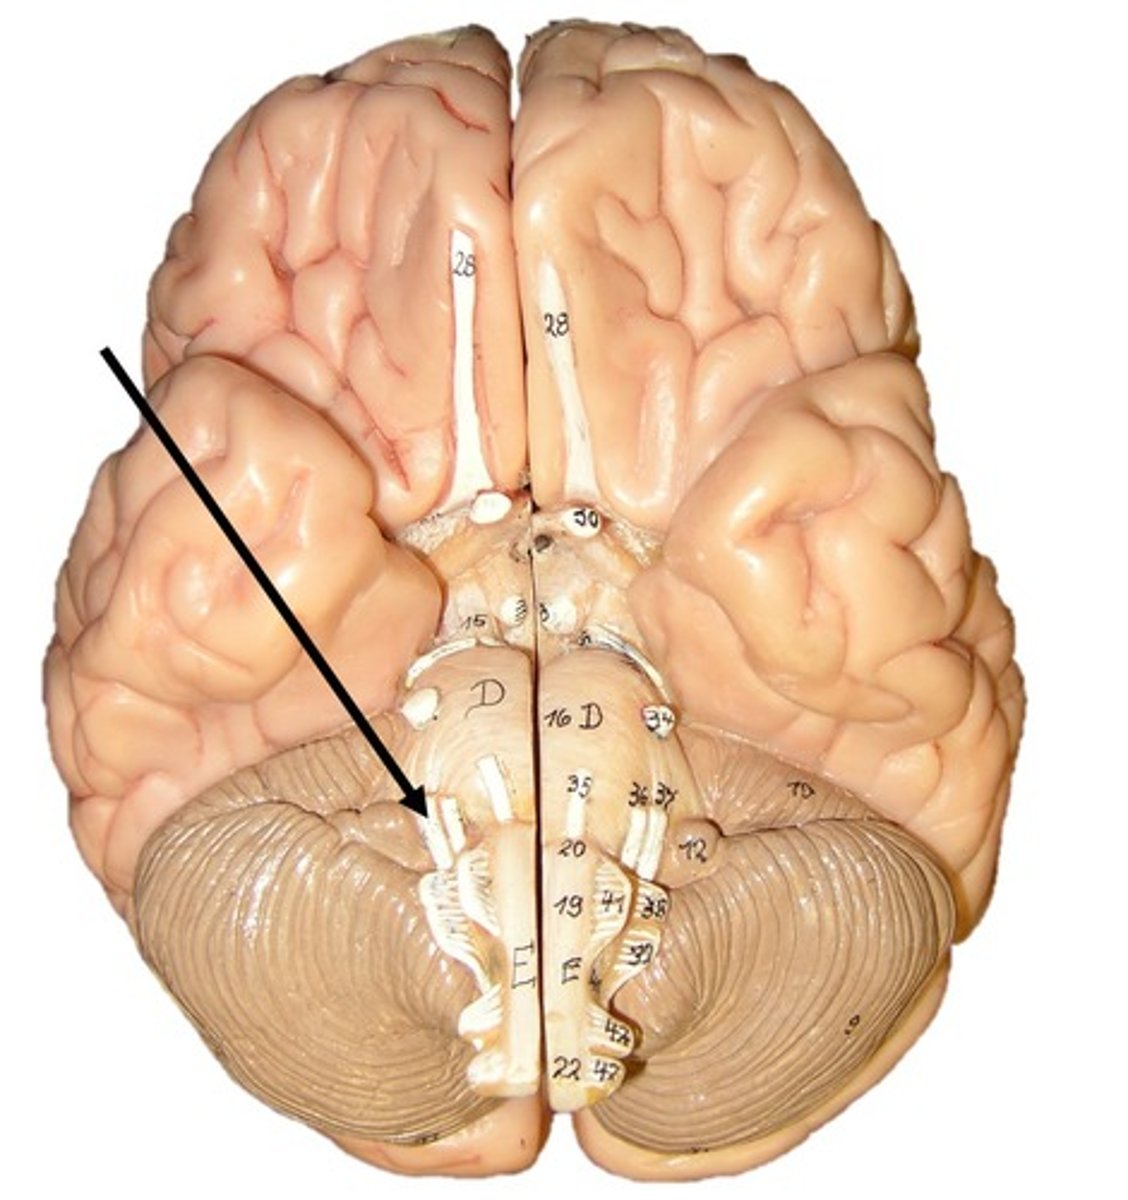

Cerebellum

anterior lobe of cerebellum

posterior lobe of cerebellum

vermis

cerebellar peduncles

arbor vitae

Primary fissure